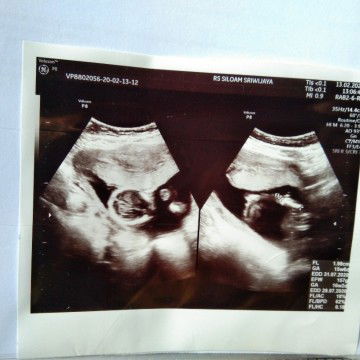

sedang mengandung

hpl 30 juli